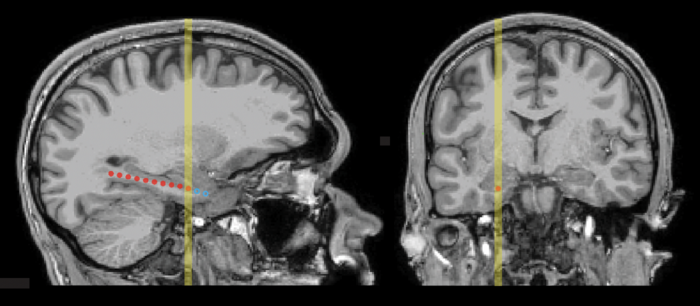

图4 MRI扫描显示典型患者(P1)矢状面和冠状面内颞电极位置。

图片来源:芝加哥大学神经外科